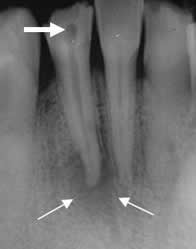

Fig 37. Enfermedad endodental.

Rx periapical. Se identifica caries. (Flecha gruesa). Extensión periapical de la infección, con disminución de la densidad del hueso que rodea las raíces. (Flechas delgadas).